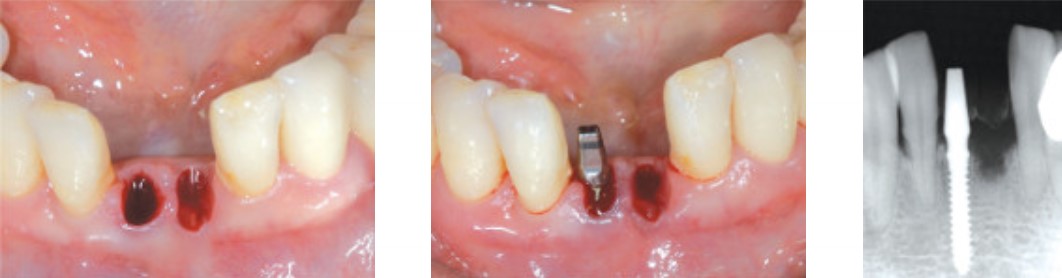

Экстракция, #41 Имплантат для узкого гребня MS

Временный протез, финальное протезирование через 4 мес.